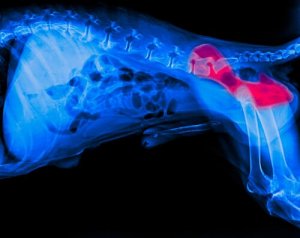

Esta é uma doença que afeta o quadril e as suas articulações. Sendo assim, ela ocorre quando há um problema na junta entre a cabeça do fêmur e sua cavidade correspondente no quadril.

Quando isso acontece, os tecidos se degradam e os cães começam a sentir desconforto ao caminhar, o que resulta em claudicação.

Se observarmos algum desses sintomas, devemos procurar um veterinário, que certamente fará um exame de raio-x para confirmar o diagnóstico.